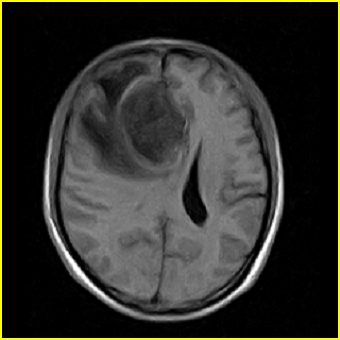

男,45岁,头部剧烈疼痛伴呕吐5天。

右侧额叶见较大的类圆形长t1信号环绕等t1环影,长t2信号环绕短等t2环,周围见明显水肿占位征,中线结构左移,男,45岁,头部剧烈疼痛伴呕吐5天。

右侧额叶,见一占位病灶,t1像病灶、水肿长t1;其间为短t1环行信号。t2像病灶、水肿长t2,其间为短t2环行信号。占位效应明显,中线左移,右测脑室受压闭塞。结合患者发病较急。首先考虑:右侧额叶脑脓肿形成。鉴别:1、转移瘤,多发多见2、胶质瘤。建议增强

t1加权肿瘤呈低信号,肿瘤壁呈等信号.t2 加权时肿瘤呈高信号,肿瘤壁呈等信号.

考虑1脑脓肿.2恶性胶质瘤.